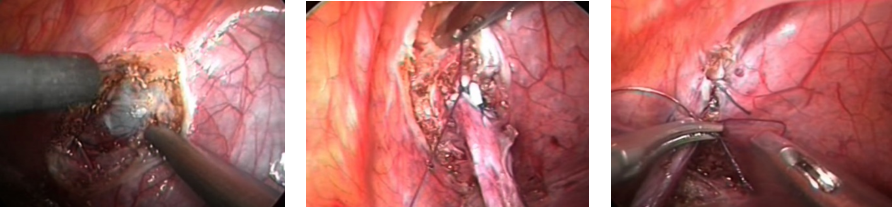

Bệnh nhân được chỉ định nội soi nong niệu quản hẹp nhưng thất bại do niệu quản hẹp khít tại vị trí cách lỗ niệu quản khoảng 4cm.Sau đó Bệnh nhân được chỉ định mổ nội soi ổ bụng cắm lại niệu quản theo phương pháp Lich – Grégoir. Phẫu thuật được thực hiện với 3 trocar (1 trocar 10mm ở rốn và 2 trocar 5mm ở 2 hố chậu) . Chỗ hẹp tại vị trí gần sát bàng quang do xơ dính của lần phẫu thuật trước.

Hình 2. Cắt mở và tách cơ bàng quang đến lớp niêm mạc ,Khâu niệu quản vào bàng quang và khâu đóng cơ bàng quang

Cắt niệu quản trên chỗ hẹp, giải phóng 2 mặt bên và mặt trước bàng quang để tạo biên độ di động bàng quang lớn hơn khi cắm niệu quản. Dùng móc đốt đánh dấu và mở phúc mạc mặt trước bên, sau đó cắt các lớp cơ bàng quang  dài khoảng 3 – 4 cm (khoảng 5 lần chiều dài đường kính ngang đoạn cuối niệu quản), bộc lộ niêm mạc bàng quang . mở niêm mạc bàng quang , khâu niêm mạc bàng quang với miệng niệu quản 1 nửa chu vi, đặt JJ sau đó khâu kín nửa còn lại. Đóng mép cơ bàng quang  phủ trên đầu dưới niệu quản bằng 3 – 4 mũi khâu rời chỉ vicryl 4.0. Chú ý tránh lấy mép cơ bàng quang  quá gần có thể làm bóp nghẹt niệu quản gây hẹp sau này, đặc biệt mũi khâu cao trên cùng. Hút hết dịch ổ bụng, đặt dẫn lưu Douglas. Bệnh nhân hậu phẫu ổn định, thông tiểu được rút vào ngày thứ 5, dẫn lưu được rút vào ngày hậu phẫu thứ 6, xuất viện vào ngày hậu phẫu thứ 7.